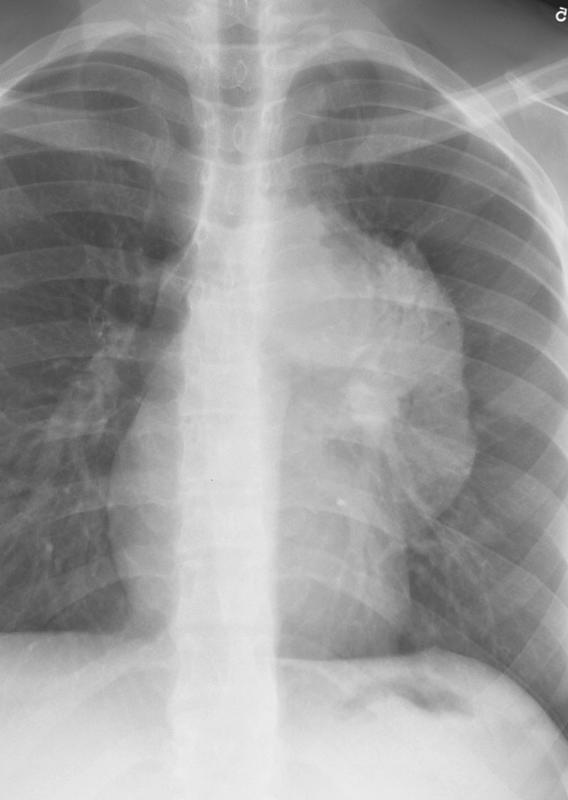

Gallery Mediastinum Lymphoma 11a

11a